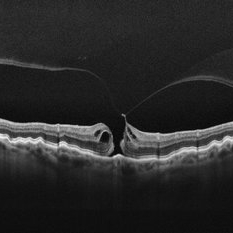

Stage 2 Macular Hole From VMT

Stage 2 Macular Hole From VMT

Mar 21 2025 by Drew Mitchell

HD 1 line 100x OCT showcasing a full thickness macular hole caused by vitreomacular traction on fovea. Choroidal folds can also be seen on scan.

Photographer: Drew Mitchell OCT-C

Imaging device: Zeiss Cirrus 6000

Condition/keywords: Choroidal Folds, FTMH, macular hole, OCT, PVD